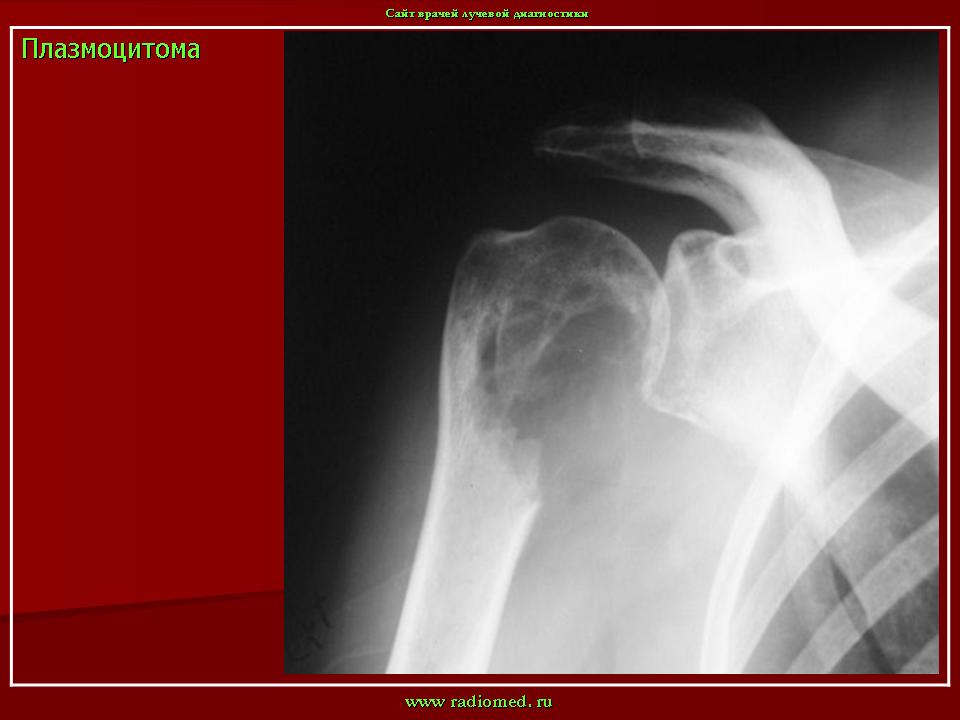

Плазмоцитома.

1.prl_.slayd38.jpg

Приложения: